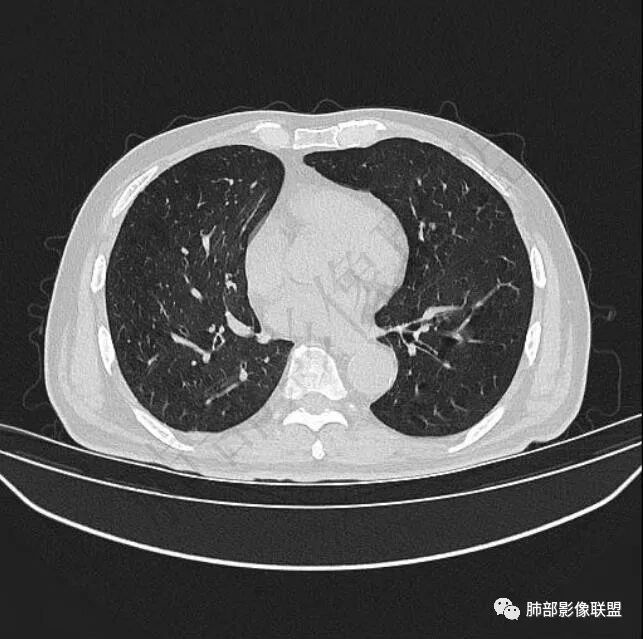

二..发现左肺上叶舌段实性密度小结节影,不规则略呈半环形,边界清楚,未见分叶、毛刺及磨玻璃晕。未见卫星病灶。